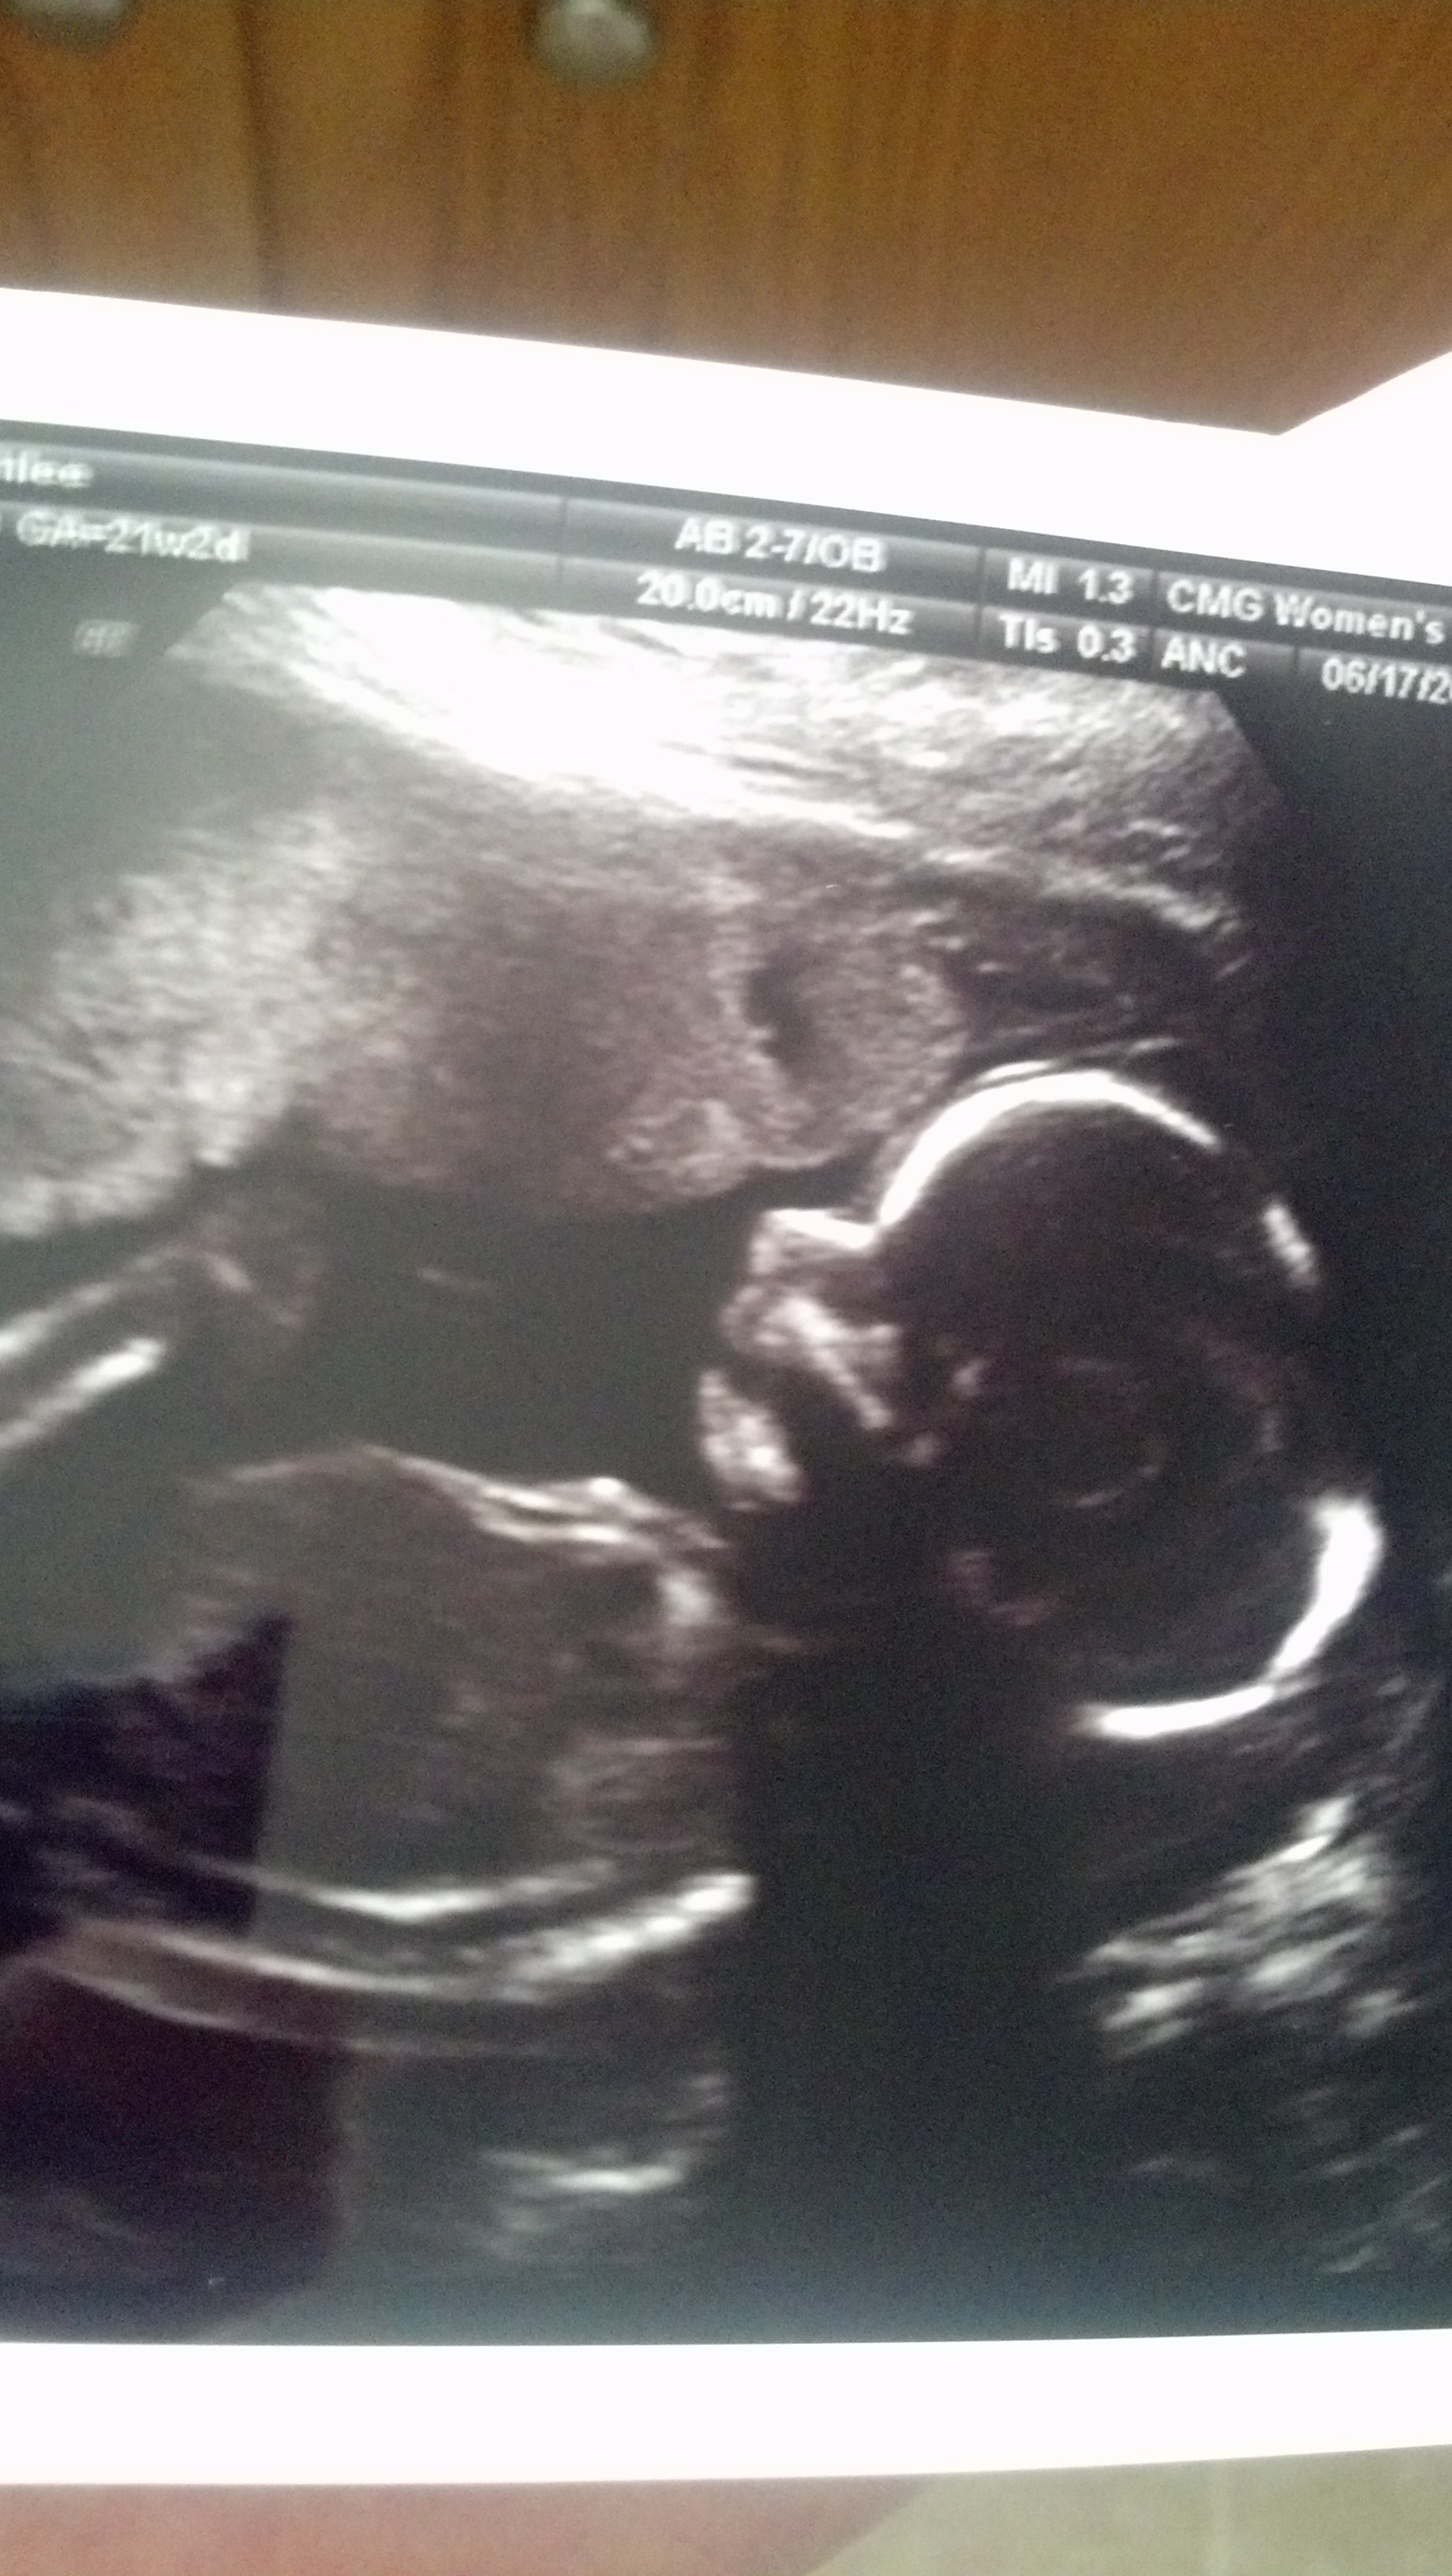

Girl! Little Elizabeth Grace (we'll be calling her Ellie. Not Lizzie). Plus all the measurements came back normal. She's a healthy little girl. We got some great profile shots. Saw her moving her mouth. She even grabbed her foot at one point. Towards the end she turned into a diva and was covering her face. So cute. And because they messed up my appointment last week, we got a free DVD of the whole thing. Plus the usual pictures